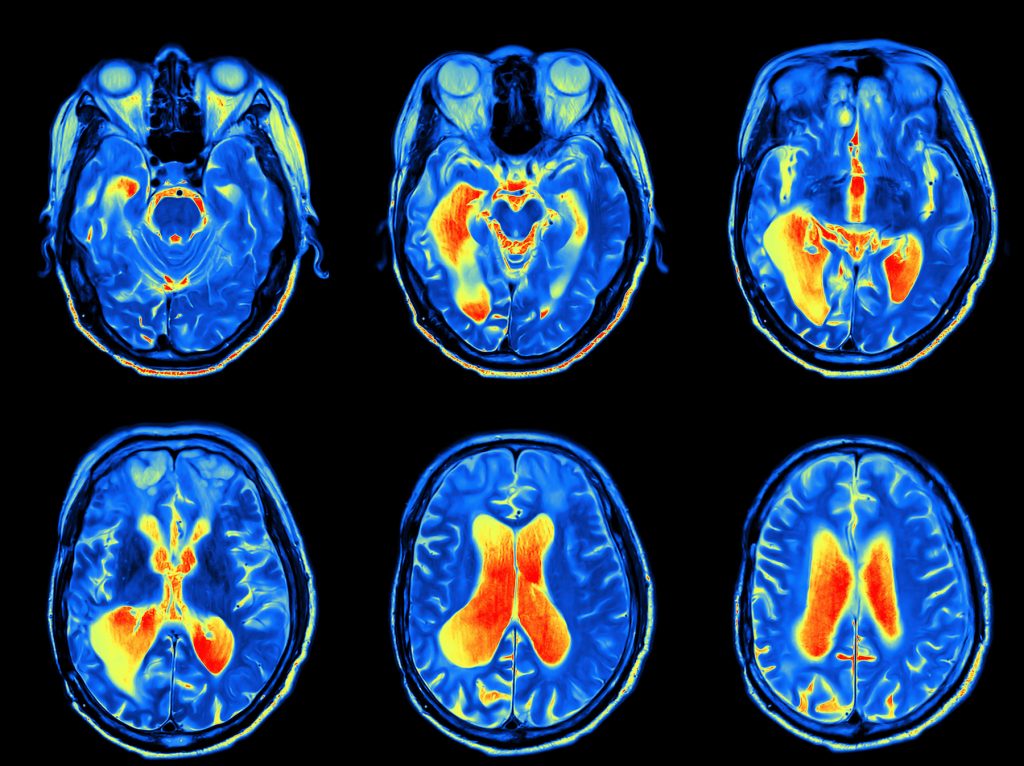

The neuropathologic findings have been controversial while the genetic mechanisms in play have been difficult to identify. Although brain volume and weight are reduced in patients with schizophrenia, there is an enlargement of the ventricles. Imaging studies suggest abnormalities in the hippocampus, neocortex, and thalamus. Some studies have demonstrated similar brain findings in relatives of a schizophrenic patient reinforcing genetic causes. One of the most interesting histological findings are clustered neurons in the lamina II of the entorhinal cortex and in the neocortical white matter. This suggests an early neurodevelopmental anomaly. Many twin studies have been conducted confirming the inheritability of this disease, with an approximate 80% risk.